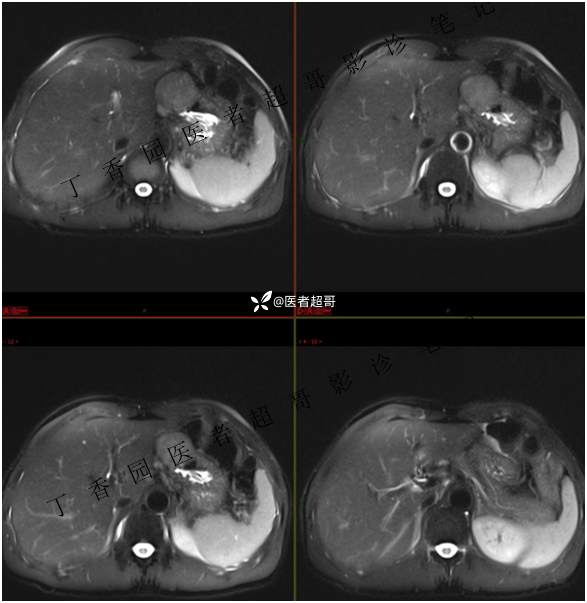

肝胃间隙肿瘤,间质瘤?平滑肌瘤?还是鞘瘤?有结果,请分析!

现病史:患者于3天前查体行肝胆脾胰肾彩超示肝内实性占位,无恶心、呕吐,无发热、寒战,无腹胀、腹泻,进一步于医院行上腹部CT增强示:肝胃交界处肿块。未行特殊治疗。今患者为求进一步治疗,来我院就诊,门诊以“肝占位性病变”收入院。患者自发病以来,神志清,精神可,饮食睡眠可,二便可,体重近期未见明显变化。